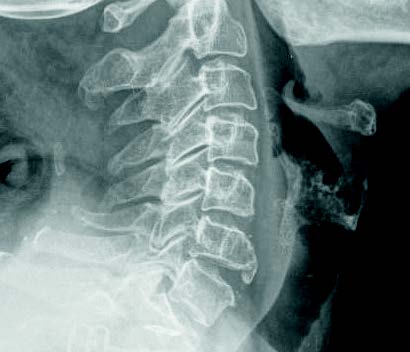

La enfermedad de Forestier, también conocida como “hiperostosis esquelética idiopática difusa” y ocasionalmente como “espondilosis hiperostótica” e “hiperostosis anquilosante” fue descrita por primera vez por Forestier y Rotes-Querol en 1950. Se definió como la osificación del ligamento longitudinal común anterior de los cuerpos vertebrales. El síntoma más común cuando está implicada la columna cervical es la disfagia, menos frecuente es la disnea, ambos síntomas secundarios a la compresión extrínseca del esófago y la tráquea.

Mujer de 59 años, que consulta por disfagia desde hace 2 años, parece como si tuviera un escalón y se le atragantara la comida, disfonías frecuentes porque habla muy fuerte. Su abuelo murió de cáncer de laringe y muchos familiares han tenido cáncer. La exploración por fibroscopia nasolaríngea está dentro de la normalidad y la palpación de cuello es normal. Se pide tránsito esofágico que demuestra una pequeña impronta en la pared posterior del esófago cervical, con disminución del calibre esofágico por engrosamiento vertebral. Se pide Rx lateral de cuello donde se confirma el osteofito de la pared anterior vertebral cervical C6. Se recomiendan revisiones periódicas y relajantes musculares si aparece contractura faríngea.